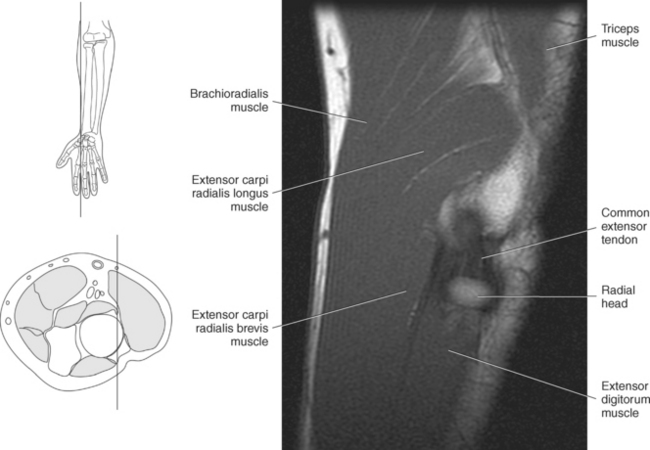

The muscles of the superficial dorsal group are demonstrated in Figures 9.87 through 9.98 and 9.100. The brachioradialis is an extensor muscle lying along the lateral border of the forearm. This large muscle arises from the upper two thirds of the supracondylar ridge of the humerus and attaches distally to the radial styloid process. The brachioradialis flexes the forearm at the elbow and assists with pronation and supination (Figure 9.100).

The extensor carpi radialis longus muscle arises just distal to the brachioradialis on the lower third of the supracondylar ridge of the humerus. It runs posterior and deep to the brachioradialis to insert on the base of the second metacarpal. It acts as an extensor and abductor of the hand at the wrist joint (Figure 9.100).

The other superficial muscles (extensor carpi radialis brevis, extensor carpi ulnaris, extensor digitorum, extensor digiti minimi) arise from a common extensor tendon attached to the lateral epicondyle of the humerus. At the level of the elbow they appear as one structure but become more distinct distally as they insert on various structures about the wrist and hand.

The extensor carpi radialis brevis has components that arise from the radial collateral and annular ligaments as well as the common extensor tendon. It runs along the dorsal surface of the wrist to insert on the base of the third metacarpal and acts to extend and abduct the hand at the wrist joint (Figure 9.100).

The extensor digitorum muscle is the main extensor of the second to fifth digits and occupies much of the posterior surface of the forearm. It arises from the common extensor tendon and divides into four individual tendinous slips just proximal to the wrist. The four tendons run in a single synovial sheath as they pass under the extensor retinaculum. The tendons insert into the extensor expansions of the second through fifth digits, helping to form the extensor hoods (see the section on ligaments of the finger). In addition, small slips of the tendon spread out and run to the bases of the proximal phalanges and to the capsules of the metacarpophalangeal joints (Figure 9.100). The extensor digitorum muscle extends and spreads the fingers and extends the hand at the wrist joint. The extensor digiti minimi muscle arises from the common extensor tendon and passes under the extensor retinaculum in its own synovial compartment. It then divides into two tendinous slips that insert on the proximal phalanx of the fifth digit to help with extension of the little finger (Figure 9.100).

The extensor carpi ulnaris is a long, slender muscle that arises from the common extensor tendon and runs along the medial and dorsal side of the ulna to insert on the base of the fifth metacarpal. Its main actions include extension of the hand at the wrist joint and adduction of the hand, resulting in ulnar deviation (Figure 9.100).